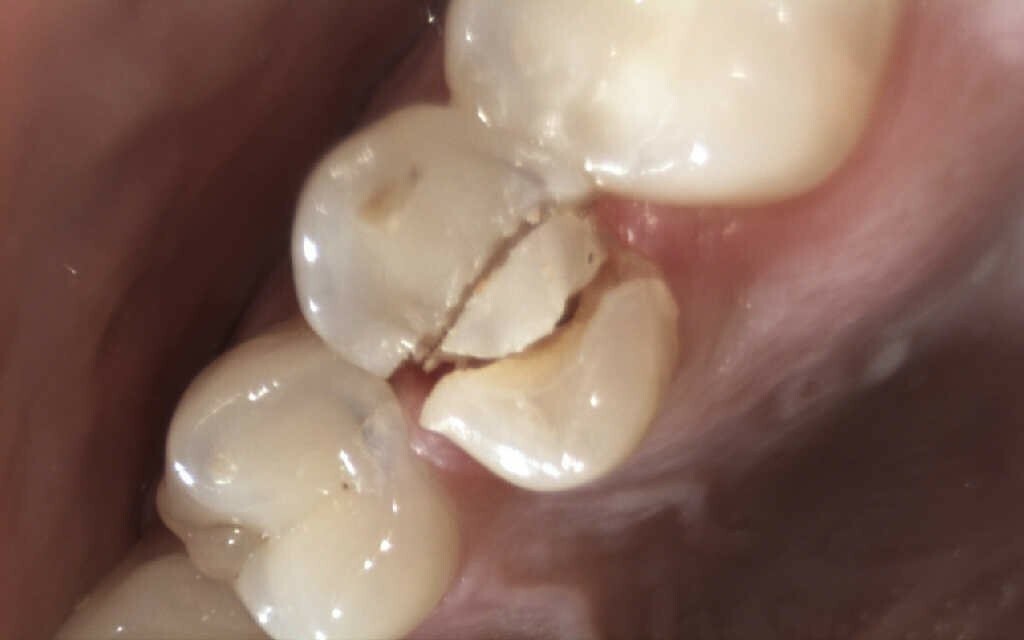

Ein Patient mit einem gepflegten Gebiss in eugnather Verzahnung (Abb. 1) stellte sich aufgrund einer Kronen-Wurzelfraktur an Zahn 25 in der Praxis vor. Die Untersuchung ergab, dass der Zahn aufgrund einer Fraktur des palatinalen Höckers mit subkrestalem Frakturverlauf (Abb. 2) nicht erhaltungswürdig war.